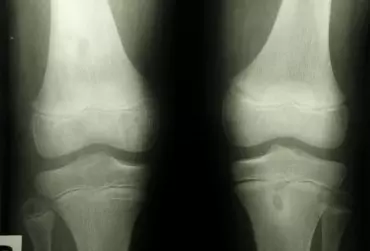

Uszkodzenia chrząstki stawowej przedziału rzepkowo-udowego

Staw rzepkowo-udowy stanowiący jeden z dwóch stawów tworzących staw kolanowy często jako pierwszy daje objawy podczas tworzących się zmian zwyrodnieniowych. Przenosząc znaczne przeciążenia podczas pracy aparatu wyprostnego kolana narażany jest w dużej mierze na uszkodzenia. Poniżej przedstawiona została grupa schorzeń częściej występujących w przedziale rzepkowo-udowym.